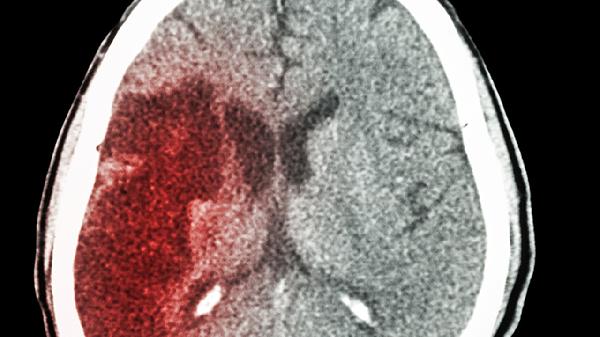

轻微脑出血一般需要1-3个月恢复,实际时间受到出血量、出血部位、基础疾病、康复治疗和年龄等因素的影响。

出血量是决定恢复速度的关键因素。少量出血小于10毫升对脑组织压迫较轻,通常1个月内可吸收;中等量出血10-30毫升需结合CT复查判断吸收情况,恢复期可能延长至2个月。出血后24小时内病情稳定者预后较好。

非功能区出血恢复较快。基底节区少量出血若未累及内囊,运动功能多在6-8周恢复;丘脑出血易影响感觉功能,需8-12周康复;小脑出血可能引起平衡障碍,需针对性前庭康复训练。